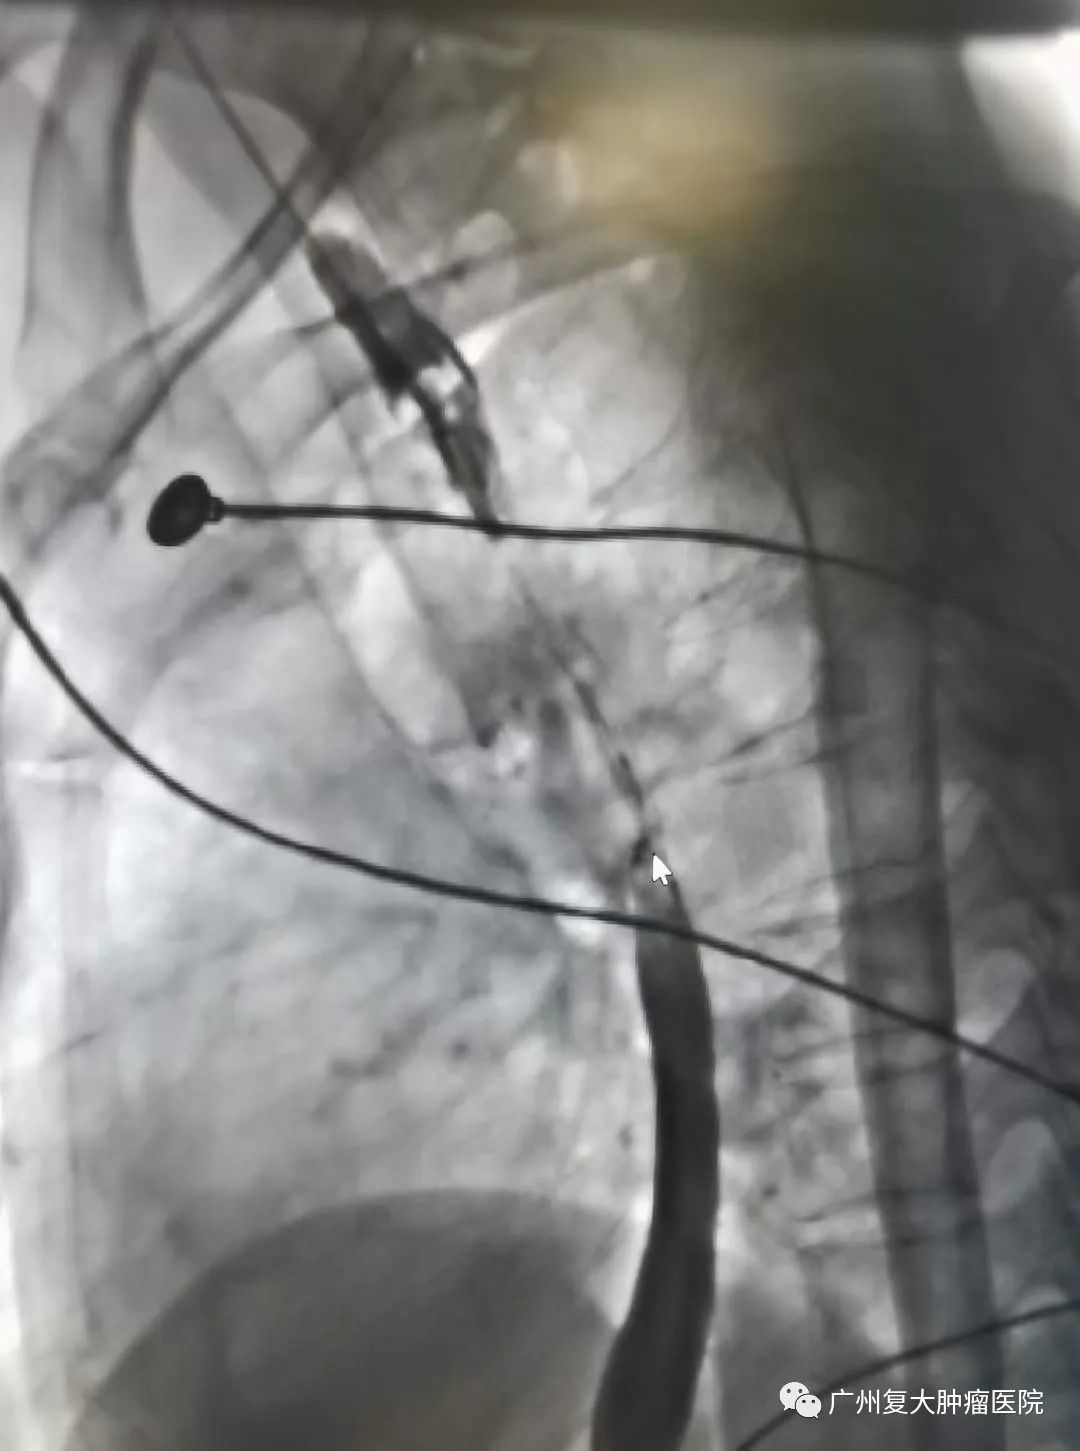

新年伊始,牛立志院长和介入科钟小军医生等医护人员在查房的过程中,收到一名食道癌患者满满的祝福。患者因食道癌并食道-气管瘘在多家大医院寻医问诊,但因带胃管两个多月,进食困难,精神萎靡,生活质量较差。为进一步诊疗,于年前28日晚来到我院,并在隔天完善相关检查后接受食道全覆膜支架置入。术后第一天便可以进食水,精神状态也明显好转。恰逢元旦来临,患者在院感受节日氛围的同时,身体状况也愈来愈好,对他们一家人来说,这不仅是最好的新年礼物,也让他们对新的一年充满新希望。为此,患者把自己亲手写的祝福送给医护人员,以表感谢之情。